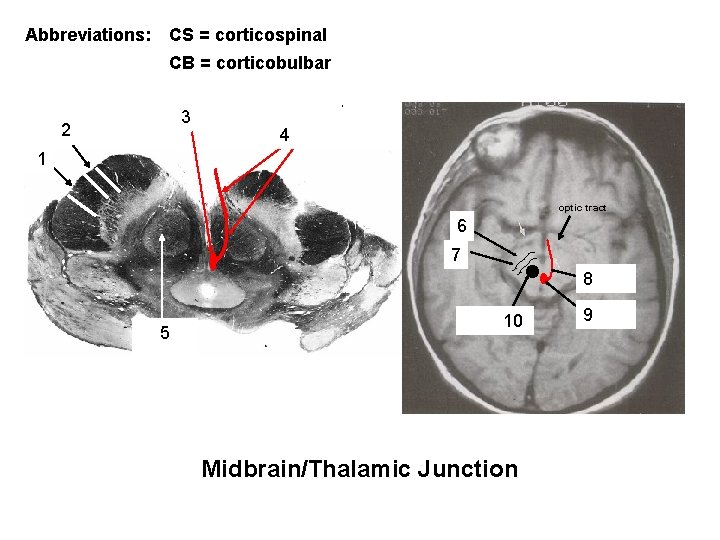

Post. limb, int. capsule: corticospinal + corticopontine 2 + thalamocortical fibers Body 3 of lateral ventricle thalamus 4 descending cortical 1 fibers in crus cerebri of midbrain 5 Ventricle III Lentiform nucleus 6 putamen is visible) (only

Abbreviations: CS = corticospinal CB = corticobulbar 2 CB Position of: oculomotor 3 nucleus + nerve roots 4 1 CS optic tract CB 6 CS 7 Oculomotor nerve roots 8 RED 5 NUCLEUS Red nucleus 10 Midbrain/Thalamic Junction Oculomotor nucleus 9